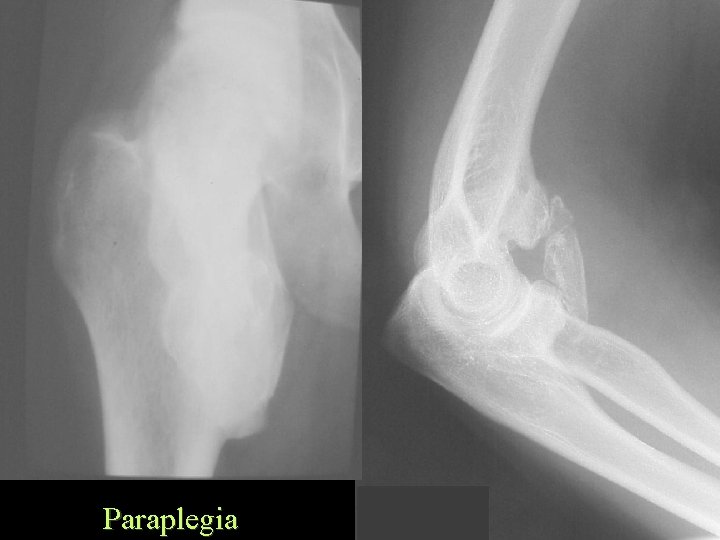

Ossification Traumatic Paraplegia • • • Approx. 40% Usually in paralyzed parts Muscles, tendons and ligaments Large joints Often causes ankylosis

Paraplegia